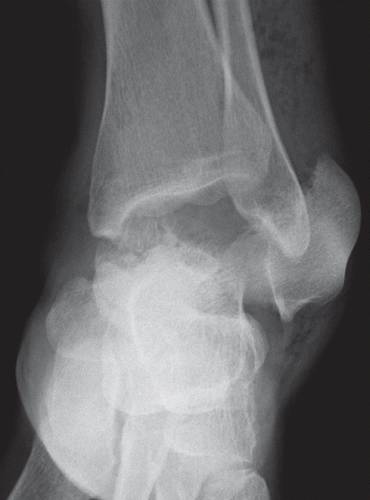

这种损伤必须与三角骨 - 一个附件后骨小梁区分开来。 在放射照相术中,后过程的断裂显示不规则的边缘(图13),而三角骨是圆形或椭圆形,具有光滑的皮质边缘(图14)。 双侧X线照片的价值有限,因为据报道三分之二的病例是双侧的(32)。 如果射线照片不确定,应进行CT。

图14 三角骨。 踝部的侧面X线片显示在距骨后方的椭圆形皮质骨化(箭头)。